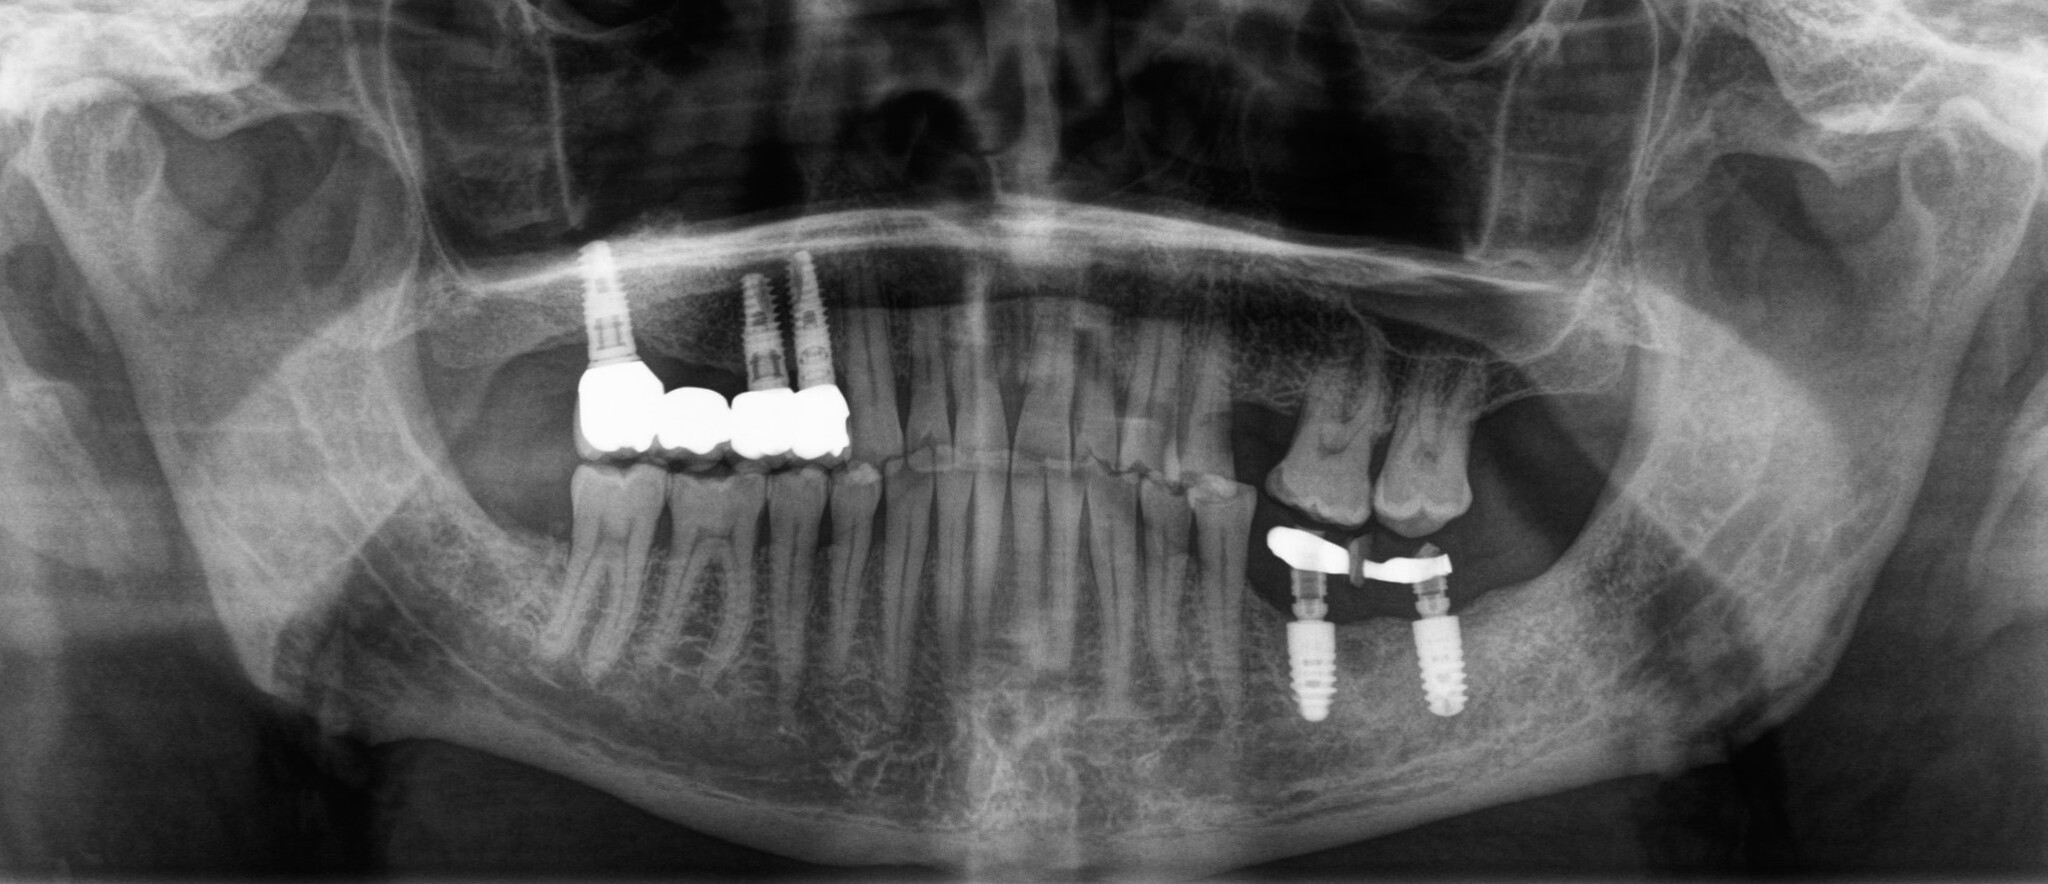

Пациент созрел на замену временных коронок постоянными на верхней челюсти справа и установку временных коронок на нижней челюсти слева:

Этот человек, как вы поняли, не поддавался объяснениям и «запугиванию», поэтому временные коронки были сделаны на металлическом основании. Они несколько прочнее.

Разницу в материалах можно видеть по белым полоскам в месте, где должна быть коронка. Если обычную временную коронку не видно, то при наличии металла на рентгеновском снимке его будет отчетливо видно.

Час замены временных коронок на постоянные (на нижней челюсти слева):

Было принято решение об удалении зуба и установке имплантатов в области 5 и 6 зубов:

Параллельно необходимо залечить 7-ку, пока нет коронок на имплнататах. Так подобраться к зубу проще.

Январь 2024. Наши дни. Установка постоянных безметалловых коронок слева сверху: